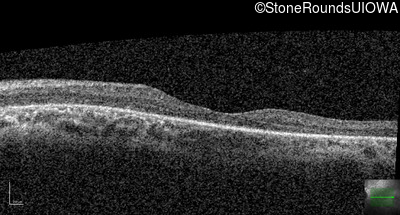

Optical Coherence Tomography - Left - 20/32

Exemplar / OCT Stack